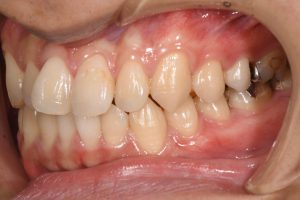

銀歯を全てセラミックにした症例

治療前

治療後

この患者様の場合

1回目にカウンセリング

2回目に型取り

3回目にセラミックのセット

の合計3回で治療終了となりました。